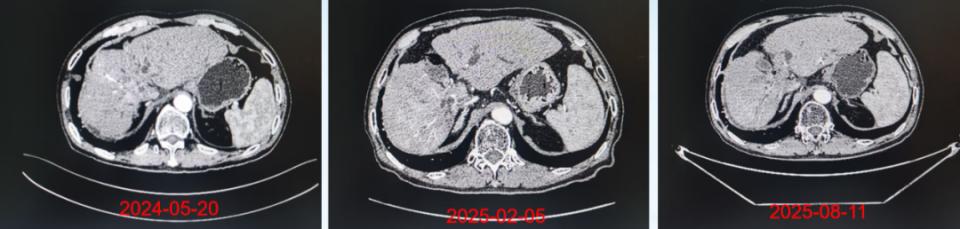

治疗随访期间肝脏CT影像学的变化

注:2024-05-20(胸部CT扫描:临床提示肝恶性肿瘤放疗后,肝左右叶胆管交界处可疑增多软组织影,肝内胆管扩张,胆管细胞癌?其内多发斑片状高密度影,胆管结石?出血?)。2025-02-05(对比2024-02-18日CT片,肝癌介入术后改变,肝右叶碘油沉积,术区病灶活性残存)。2025-08-11(肝癌介入术后病史,对比2023-05-24上腹部增强CT、胸部CT,肝癌介入术后改变,肝右叶病灶范围较前稍增大并不均匀强化,提示活性残存可能,其内碘油沉积稍减少)